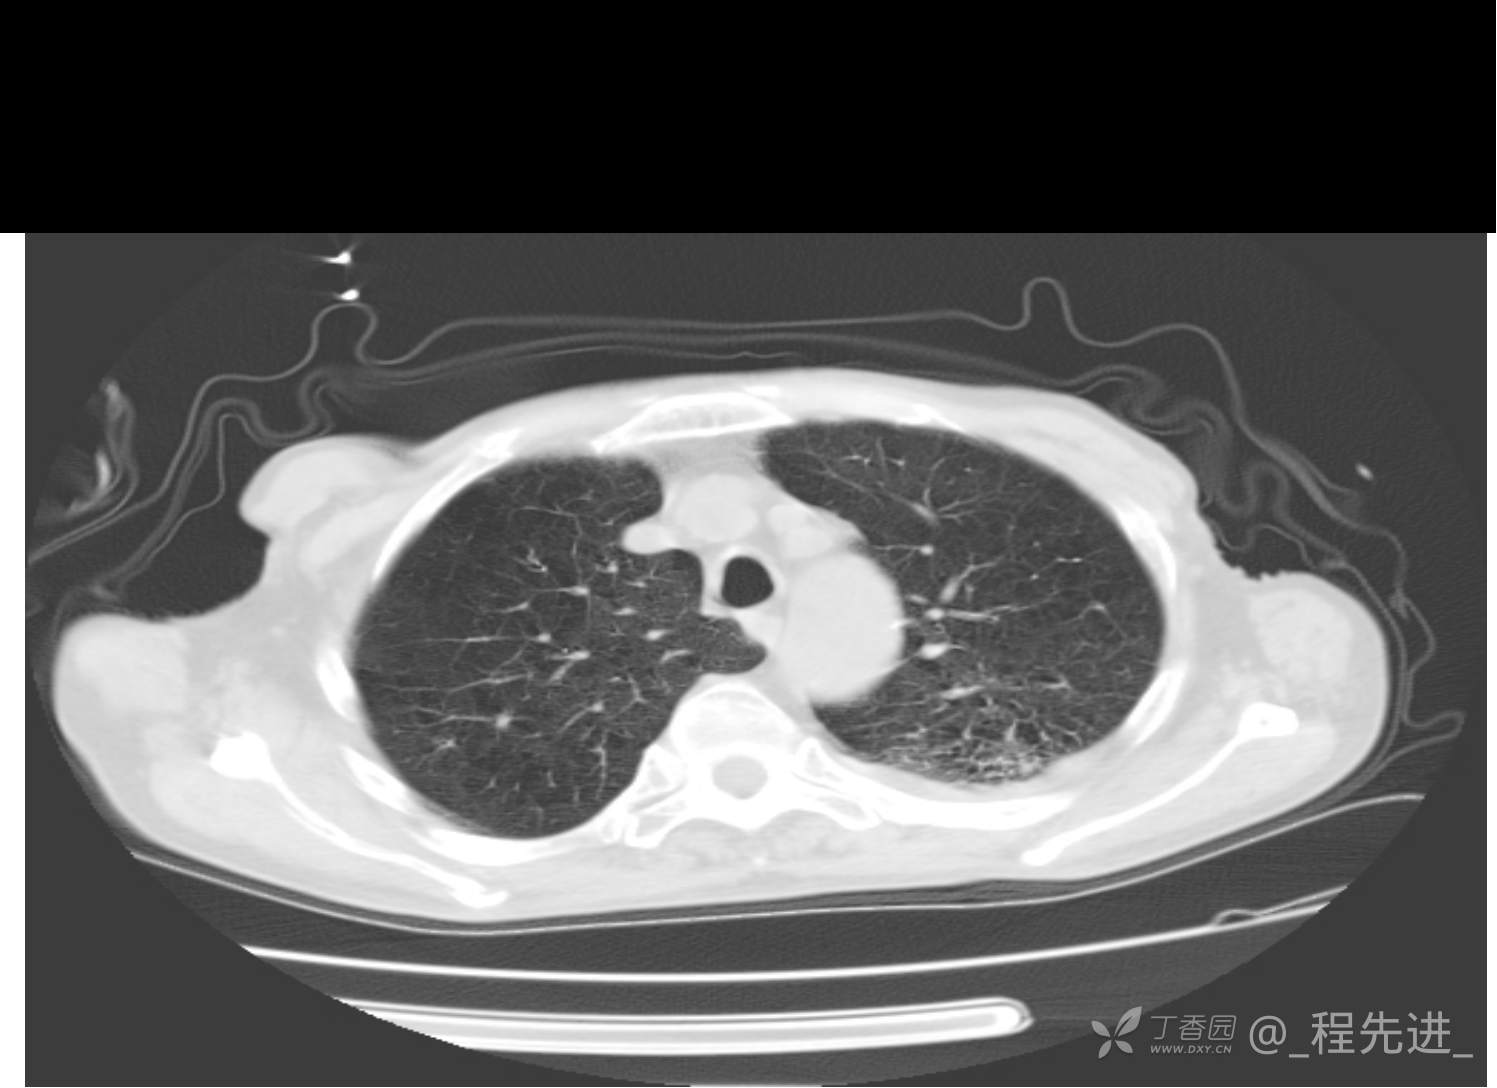

患者性别:男

患者年龄:81岁

简要病史:反复咳嗽、咳痰20余年,加重1周。两肺呼吸音低,可闻及散在干湿啰音。